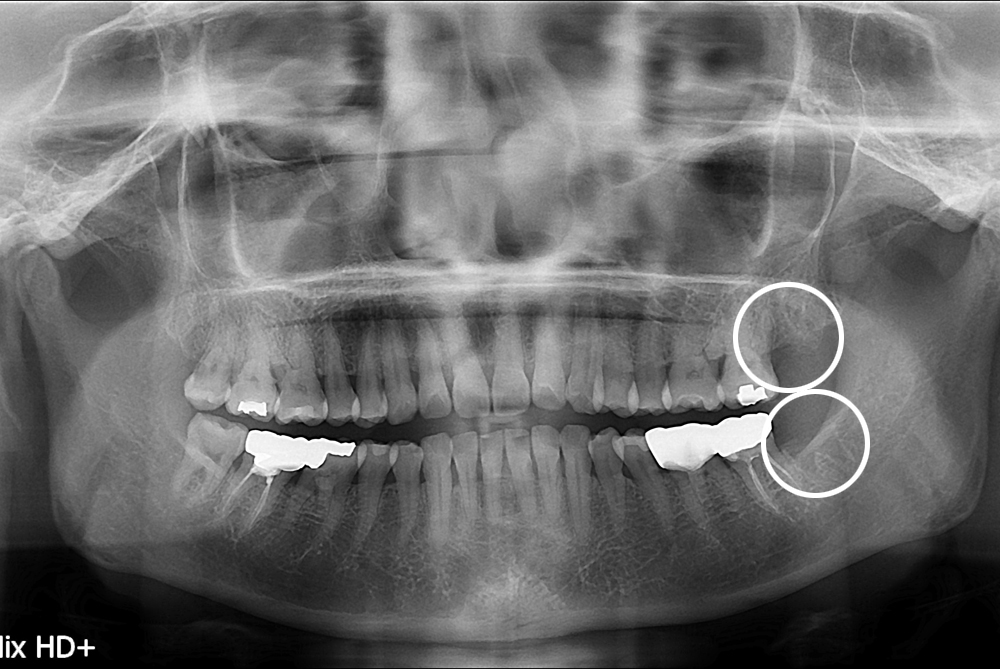

[사랑니] 난발치 사랑니 발치

치료후 : 2017-08-29

세종치과는 구강악안면외과학 박사이신 원장님이 발치하는 치과입니다.